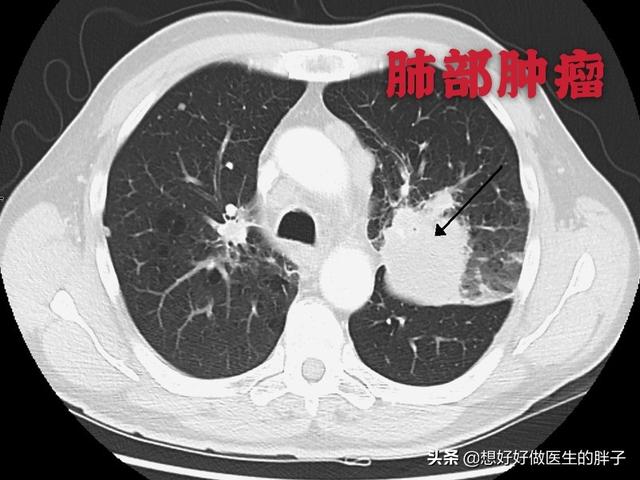

Quels sont les symptômes des métastases osseuses ? Le premier symptôme est la douleur. Le site de la métastase osseuse ressentira une douleur due à la destruction de l'os, qui peut ne pas présenter de symptômes évidents ou une douleur intermittente au début, mais comme la tumeur détruit l'os normal de manière progressive et s'aggrave peu à peu, la douleur dans le site métastatique s'aggravera également progressivement. Sur le plan clinique, il arrive que nous rencontrions un cas de douleur osseuse dans une certaine partie du corps, qui résulte d'une métastase osseuse d'une tumeur maligne. Il y a quelque temps, j'ai rencontré un cas, 40 ans, douleur à l'épaule, j'ai pensé à une épaule gelée, j'ai frotté quelques jours d'huile médicinale sans voir d'amélioration, mais de plus en plus de douleur, alors je suis allé à l'hôpital pour un examen, j'ai fait une imagerie par résonance magnétique, l'omoplate a été mangée par un morceau de (tumeur), considérant qu'il s'agissait d'une métastase osseuse, puis j'ai fait un scanner thoracique, un nodule dans le poumon droit, puis j'ai fait une biopsie pour faire la pathologie, qui était une métastase osseuse d'un cancer du poumon. Les informations sont les suivantes.

Un homme de 46 ans a été vu en consultation pour une douleur persistante dans le bas du dos. On pensait que cette douleur était due à une hernie discale. Une radiographie a été effectuée et n'a révélé aucune anomalie. Les métastases osseuses provoquant une légère destruction osseuse sont invisibles à la radiographie, de même qu'une hernie discale. Je n'ai donc pas particulièrement pensé à la possibilité d'une métastase. Une semaine plus tard, comme il n'y avait toujours pas d'amélioration, il est venu passer un scanner et a découvert qu'une vertèbre lombaire avait été rongée. En voyant une telle image, le médecin spécialiste de l'imagerie a dû penser à la possibilité de métastases et a suggéré au patient de passer un scanner du thorax, et effectivement, il y avait une masse dans les poumons, qui a été considérée comme une métastase osseuse d'un cancer du poumon, ce qui a été confirmé par la pathologie plus tard.